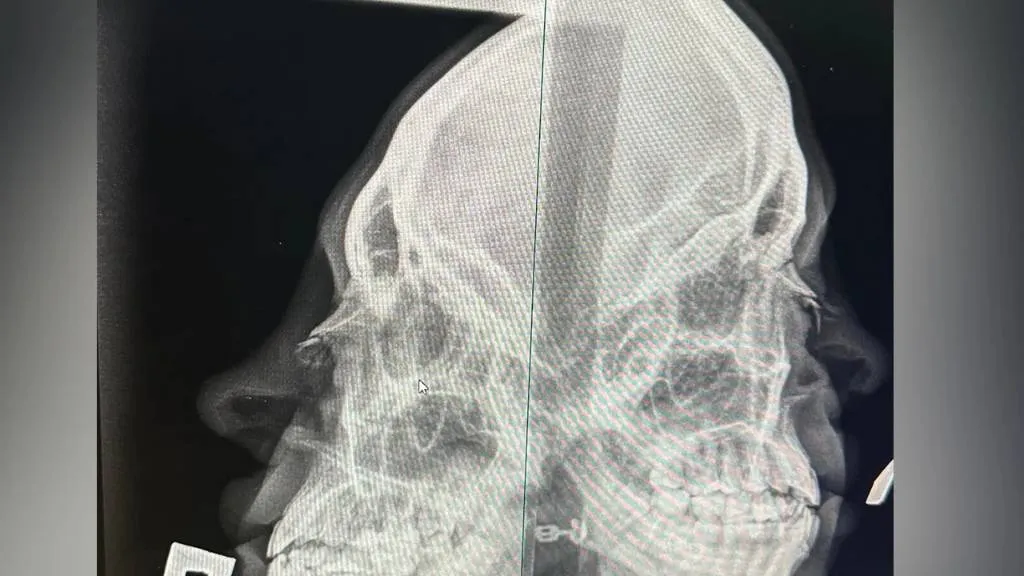

В Челябинске посетитель бара Bla Bla Bar, разозлившись из-за того, что его не пустили в заведение, сломал нос девушке-хостес и сбежал. Как сообщает SHOT, всё произошло минувшей ночью.